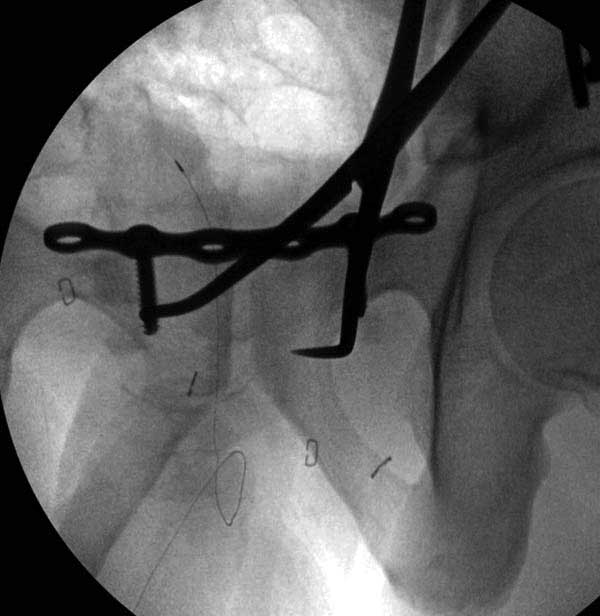

Здесь представлен случай 38 летнего больного (падение с высоты 9 метров) с нарушением тазового кольца. При поступлении для стабилизации передне-нижний аппарат наружной фиксации и на 6й день, вчера, операция из двух доступов.

Представлены снимки техники проведения стержней. Через место прикрепления прямой мышцы в Inferior Iliac Spine в направления вырезки создается жесткость. Weber clamp изнутри таза для репозиции, и фиксация после репозиции перелома крыла подвздошной кости. Наружный аппарат удален, нагрузка предполагается через два месяца.